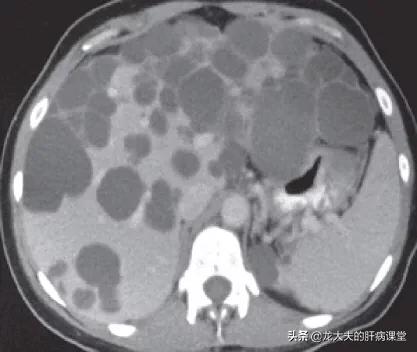

ほとんどの患者さんでは、肝嚢胞は小さく、数も多く、無症状であり、治療の必要はありません。しかし、年1回の検診の必要性を認識しておくことは重要である!なぜなら、単純な肝嚢胞に比べて、多嚢胞性肝は大きくなりやすく、腹部臓器を圧迫する症状が現れやすいからです。例えば、巨大な肝嚢胞が胃壁を圧迫し、食後の膨満感や息切れなどの症状を引き起こす患者さんも少なからずいます。

嚢胞が大きくなり続けると、腹腔内臓器が圧迫され、圧迫症状が現れます。しかし、多嚢胞性肝の場合、嚢胞が肝臓のほぼ全体を占めると肝機能異常が起こり、最終的には肝移植が必要になることもあります。しかし、一般的に多嚢胞性肝嚢胞が肝機能に影響を及ぼすことはほとんどありません。

臨床では、多発性肝嚢胞を多発性嚢胞性肝と呼ぶことが多く、患者の約50%以上が腎嚢胞、肝嚢胞を有し、少数の肝嚢胞患者は病変が肝臓の1葉または半肝部に限局していると推定される。肝嚢胞は通常、非寄生性肝嚢胞と呼ばれる。その病態の真の原因は未だ不明であり、臨床の現場では病態が著しく増加する傾向にあるが、これは最近の患者が健康診断を重要視するようになったことや、超音波、CTなどの画像診断法の普及が関係しているのではないかと考える専門家も多い。